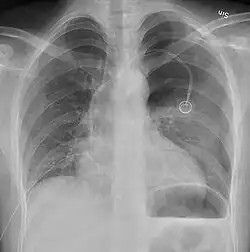

Chest X-ray

A plain chest radiograph, ideally with the X-ray beams being projected from the back (posteroanterior, or "PA"), and during maximal inspiration (holding one's breath), is the most appropriate first investigation.[35] It is not believed that routinely taking images during expiration would confer any benefit.[36] Still, they may be useful in the detection of a pneumothorax when clinical suspicion is high but yet an inspiratory radiograph appears normal.[37] Also, if the PA X-ray does not show a pneumothorax but there is a strong suspicion of one, lateral X-rays (with beams projecting from the side) may be performed, but this is not routine practice.[18][22]

Chest X-ray showing a pneumothorax on the right (left in the image), where the absence of lung markings indicates that there is free air inside the chest -

Chest X-ray showing the features of pneumothorax on the left side of the person (right in image)

The size of the pneumothorax (i.e. the volume of air in the pleural space) can be determined with a reasonable degree of accuracy by measuring the distance between the chest wall and the lung. This is relevant to treatment, as smaller pneumothoraces may be managed differently. An air rim of 2 cm means that the pneumothorax occupies about 50% of the hemithorax.[18] British professional guidelines have traditionally stated that the measurement should be performed at the level of the hilum (where blood vessels and airways enter the lung) with 2 cm as the cutoff,[18] while American guidelines state that the measurement should be done at the apex (top) of the lung with 3 cm differentiating between a "small" and a "large" pneumothorax.[38] The latter method may overestimate the size of a pneumothorax if it is located mainly at the apex, which is a common occurrence.[18] The various methods correlate poorly but are the best easily available ways of estimating pneumothorax size.[18][22] CT scanning (see below) can provide a more accurate determination of the size of the pneumothorax, but its routine use in this setting is not recommended.[38]

Not all pneumothoraces are uniform; some only form a pocket of air in a particular place in the chest.[18] Small amounts of fluid may be noted on the chest X-ray (hydropneumothorax); this may be blood (hemopneumothorax).[16] In some cases, the only significant abnormality may be the "deep sulcus sign", in which the normally small space between the chest wall and the diaphragm appears enlarged due to the abnormal presence of fluid.[19]